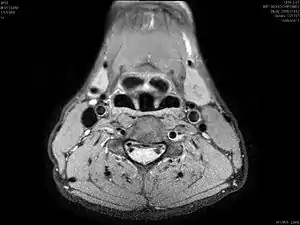

کالبدشناسی

حنجره شامل پردههای صوتی، و مشتمل بر ۹ عدد غضروف میباشد که عبارتند از: